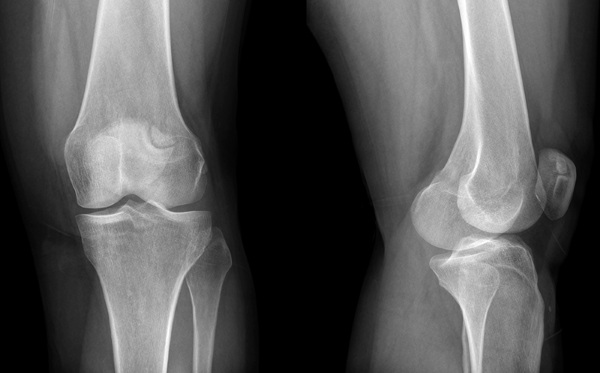

Рентгенография сустава необходима, чтобы исключить переломы или вывихи, а также другие нарушения целостности конечностей. Этот метод также используют и при проведении нагрузочных проб. При необходимости исследование дополняют томографией. Послойное исследование дает более четкую картину о состоянии костных структур.